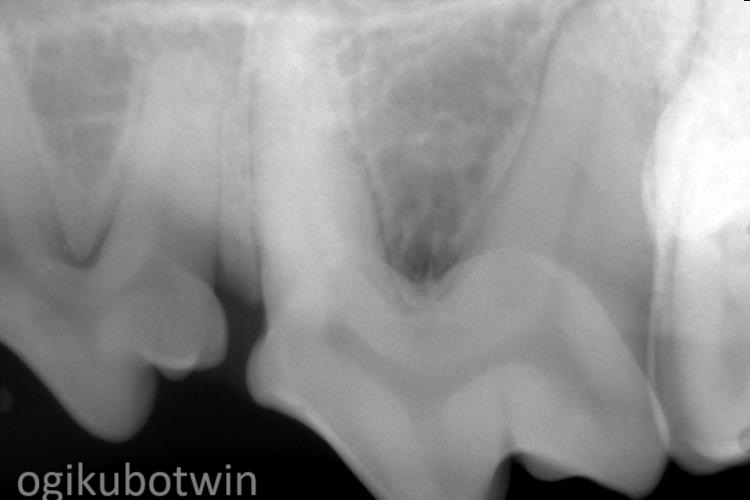

まず、全身麻酔下にて歯科レントゲンを撮影し、歯石除去を行いました。

第四前臼歯は右側の方が歯周病は進行しており、歯肉でフラップを形成し、エムドゲインを注入し再生治療を行いました。

その後継続して歯磨きを行ってもらい、8か月後に鎮静下でレントゲンを撮影し状況を確認しましたが、経過良好で治療終了となりました。